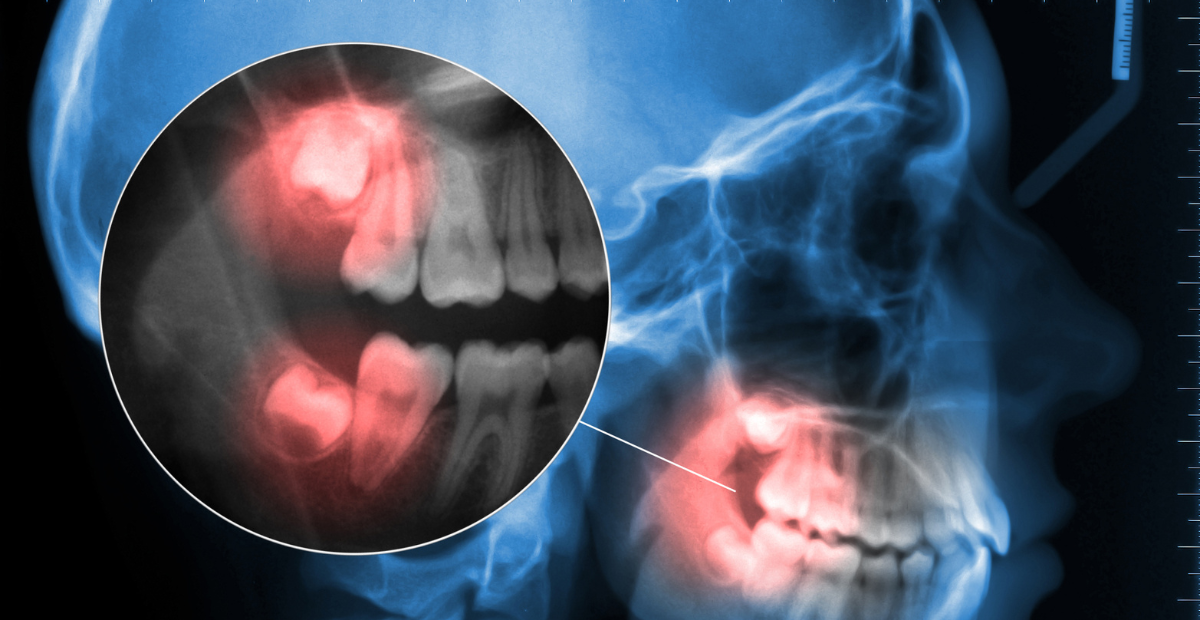

Una muela retenida es un diente que no ha podido erupcionar de forma completa en su posición habitual. Esto ocurre con mayor frecuencia en las muelas del juicio (terceros molares), aunque también puede afectar a otros dientes como premolares o caninos.

Dependiendo del caso, la muela puede estar completamente cubierta por encía o hueso (retención total) o asomar parcialmente (retención parcial), lo que puede facilitar la acumulación de bacterias y complicaciones posteriores.

El diente no es visible, ya que está completamente cubierto por hueso o encía.

Una parte de la muela ha erupcionado, pero el resto permanece bloqueado.

La muela está rodeada por hueso en su totalidad.

En consulta, el diagnóstico se realiza mediante examen clínico y una radiografía panorámica o TAC, que permite observar la posición exacta del diente y su relación con el resto de estructuras orales.